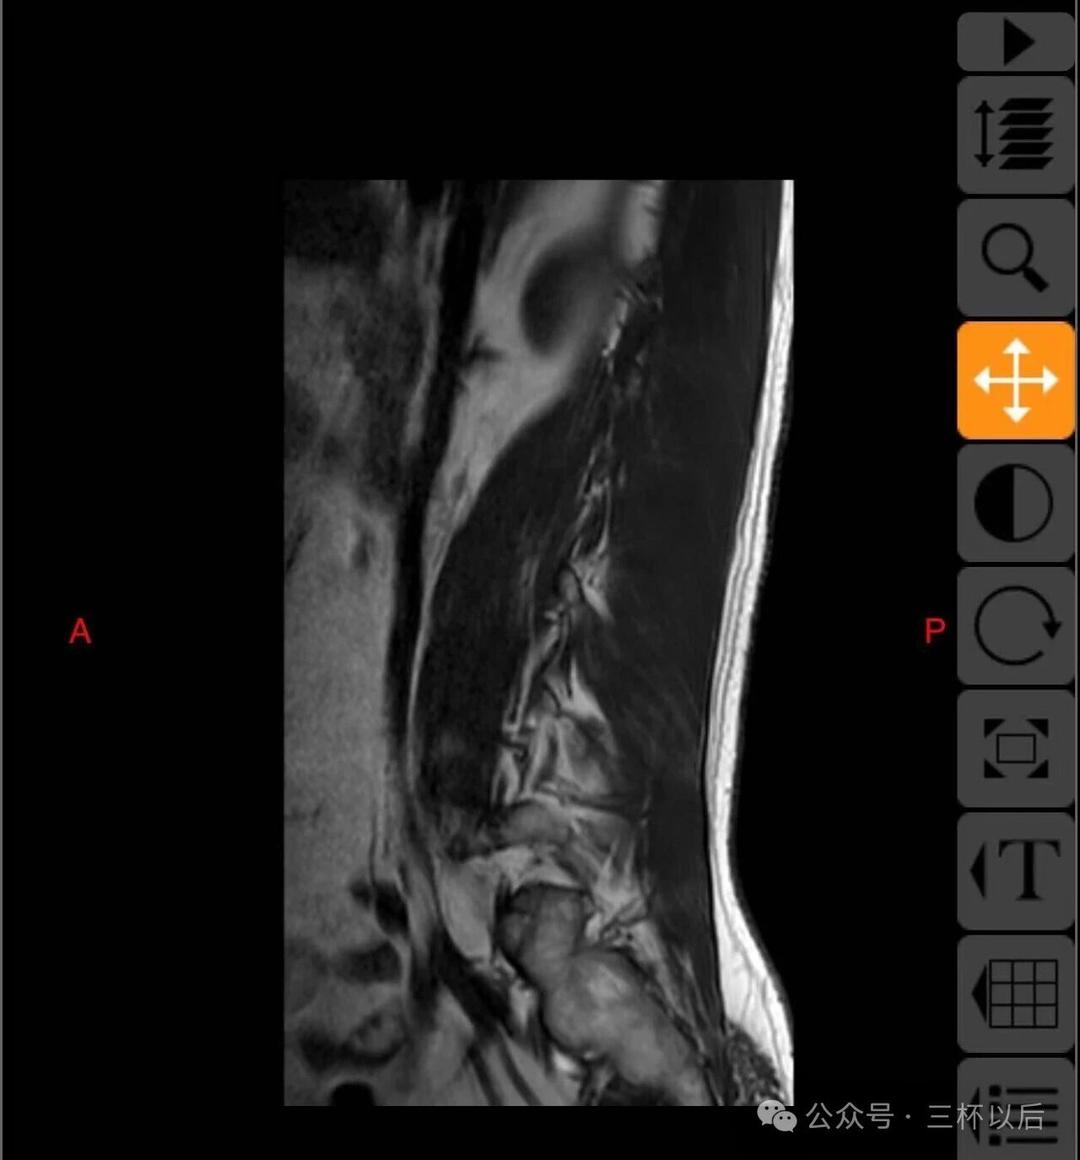

顺便贴一下拍的片子,如果有懂行的欢迎给我建议,我听劝的。真真希望能恢复如初,现在每天都能感受到疼痛,用了各种办法也不管用。